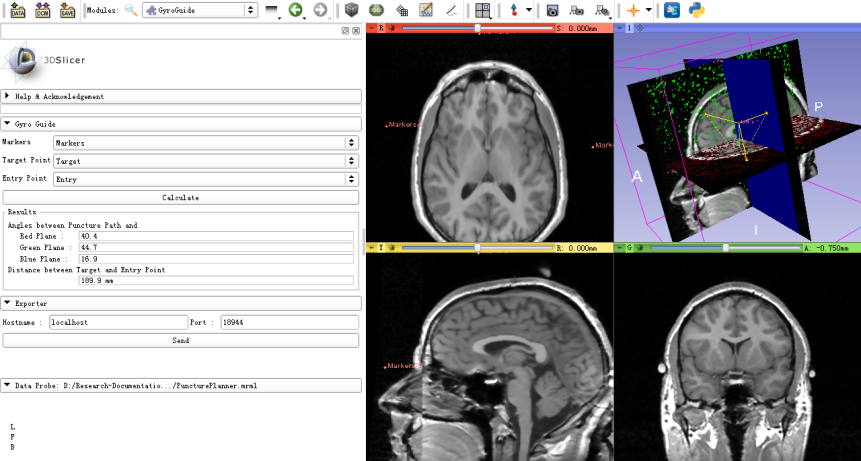

- The module should be used in cooperation with “Markups” module. First, it is required to choose five fiducial points to define two mutually-perpendicular planes as the Registration Markers. Second, set a target point and an entry point. Third, click the “Calculate” button to obtain the puncture path information, including the puncture depth and the angles between the puncture path and the reference planes. Finally, these results are displayed on a monitor or transmitted to the gyroscope-based device to assist the surgical operation.

Puncture surgery (e.g. endoscopic insertion) is a typical example to show the use of this module. This module calculates the distance of the puncture path and the angle between the probe and the reference planes. The module can also transmit the calculation results to the gyroscope-based device to facilitate the surgical operation.Tutorials

- 1 Load MRI/CT images of brain

- 2 Define “Markers”, “Target Point” and “Entry Point” using the Markups module.

- 3 Load the defined fiducial lists

- Select GyroGuide module

- 1 Select the fiducial list - Markers as the markers which define the reference planes.

- 2 Select the fiducial list – Target as the target point

- 3 Select the fiducial list – Entry as the entry point

- 4 Calculate puncture path information

- Click the “Calculate” button. The puncture path information will be displayed in the “Results” section.

- 5 Export the results

- Input IP address and port of the puncture instrument in the “Exporter” panel. Click “Send”. The calculated puncture path information could be transmitted to the gyroscope-based device to facilitate the surgical operation.